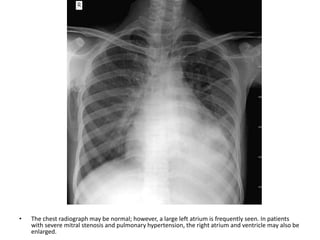

• The chest radiograph may be normal; however, a large left atrium is frequently seen. In patients

with severe mitral stenosis and pulmonary hypertension, the right atrium and ventricle may also be

enlarged.